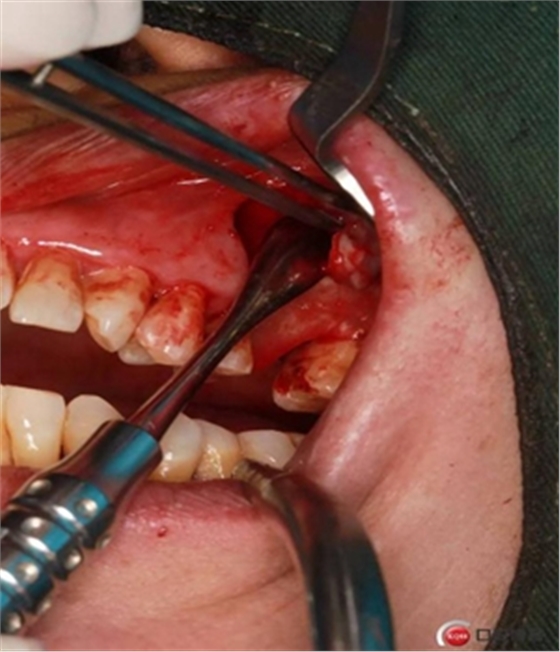

大家好,我是梁老師的助理小依。由于梁老師每天手術(shù)檔期安排較滿,加上經(jīng)常出差講課,沒有時間整理病例 。為了方便大家更及時的了解梁老師最新手術(shù)動態(tài),以后將由我為大家整理并推送梁老師最新經(jīng)典案例。案例文字旁白少,但圖片會盡量完整展示手術(shù)全過程,供大家學(xué)習(xí)參考。有任何問題,可以留言,梁老師會親自為大家解答。感謝大家對梁老師的支持和關(guān)注!